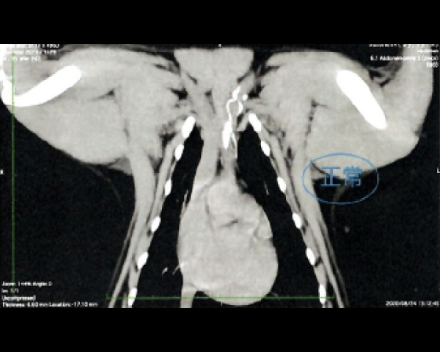

造影CT検査にて腫瘤の浸潤を評価

造影CT検査にて腫瘤の浸潤・転移を評価